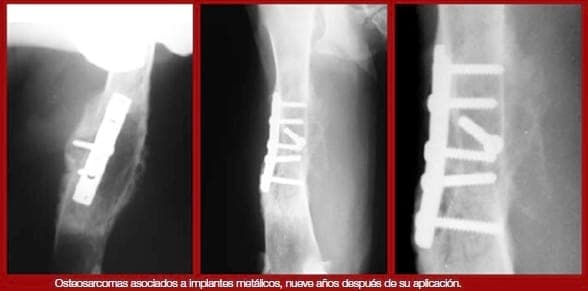

Osteosarcomas

La aparición de osteosarcomas asociados a placas es una complicación poco frecuente en traumatología veterinaria. Se han descrito casos de aparición de osteosarcomas en focos de fractura, normalmente varios años después de la aplicación de implantes metálicos, y hay autores que proponen la relación entre infecciones subclínicas de implantes metálicos y la aparición de tumores.

Históricamente la AO ha recomendado la retirada de todas las placas de los huesos. Desde un punto de vista clínico, las placas deben ser retiradas en casos de osteomielitis, dolor a la palpación de la placa, cojeras inexplicables asociadas al implante y osteopenia radiográficamente aparente asociada a la placa.